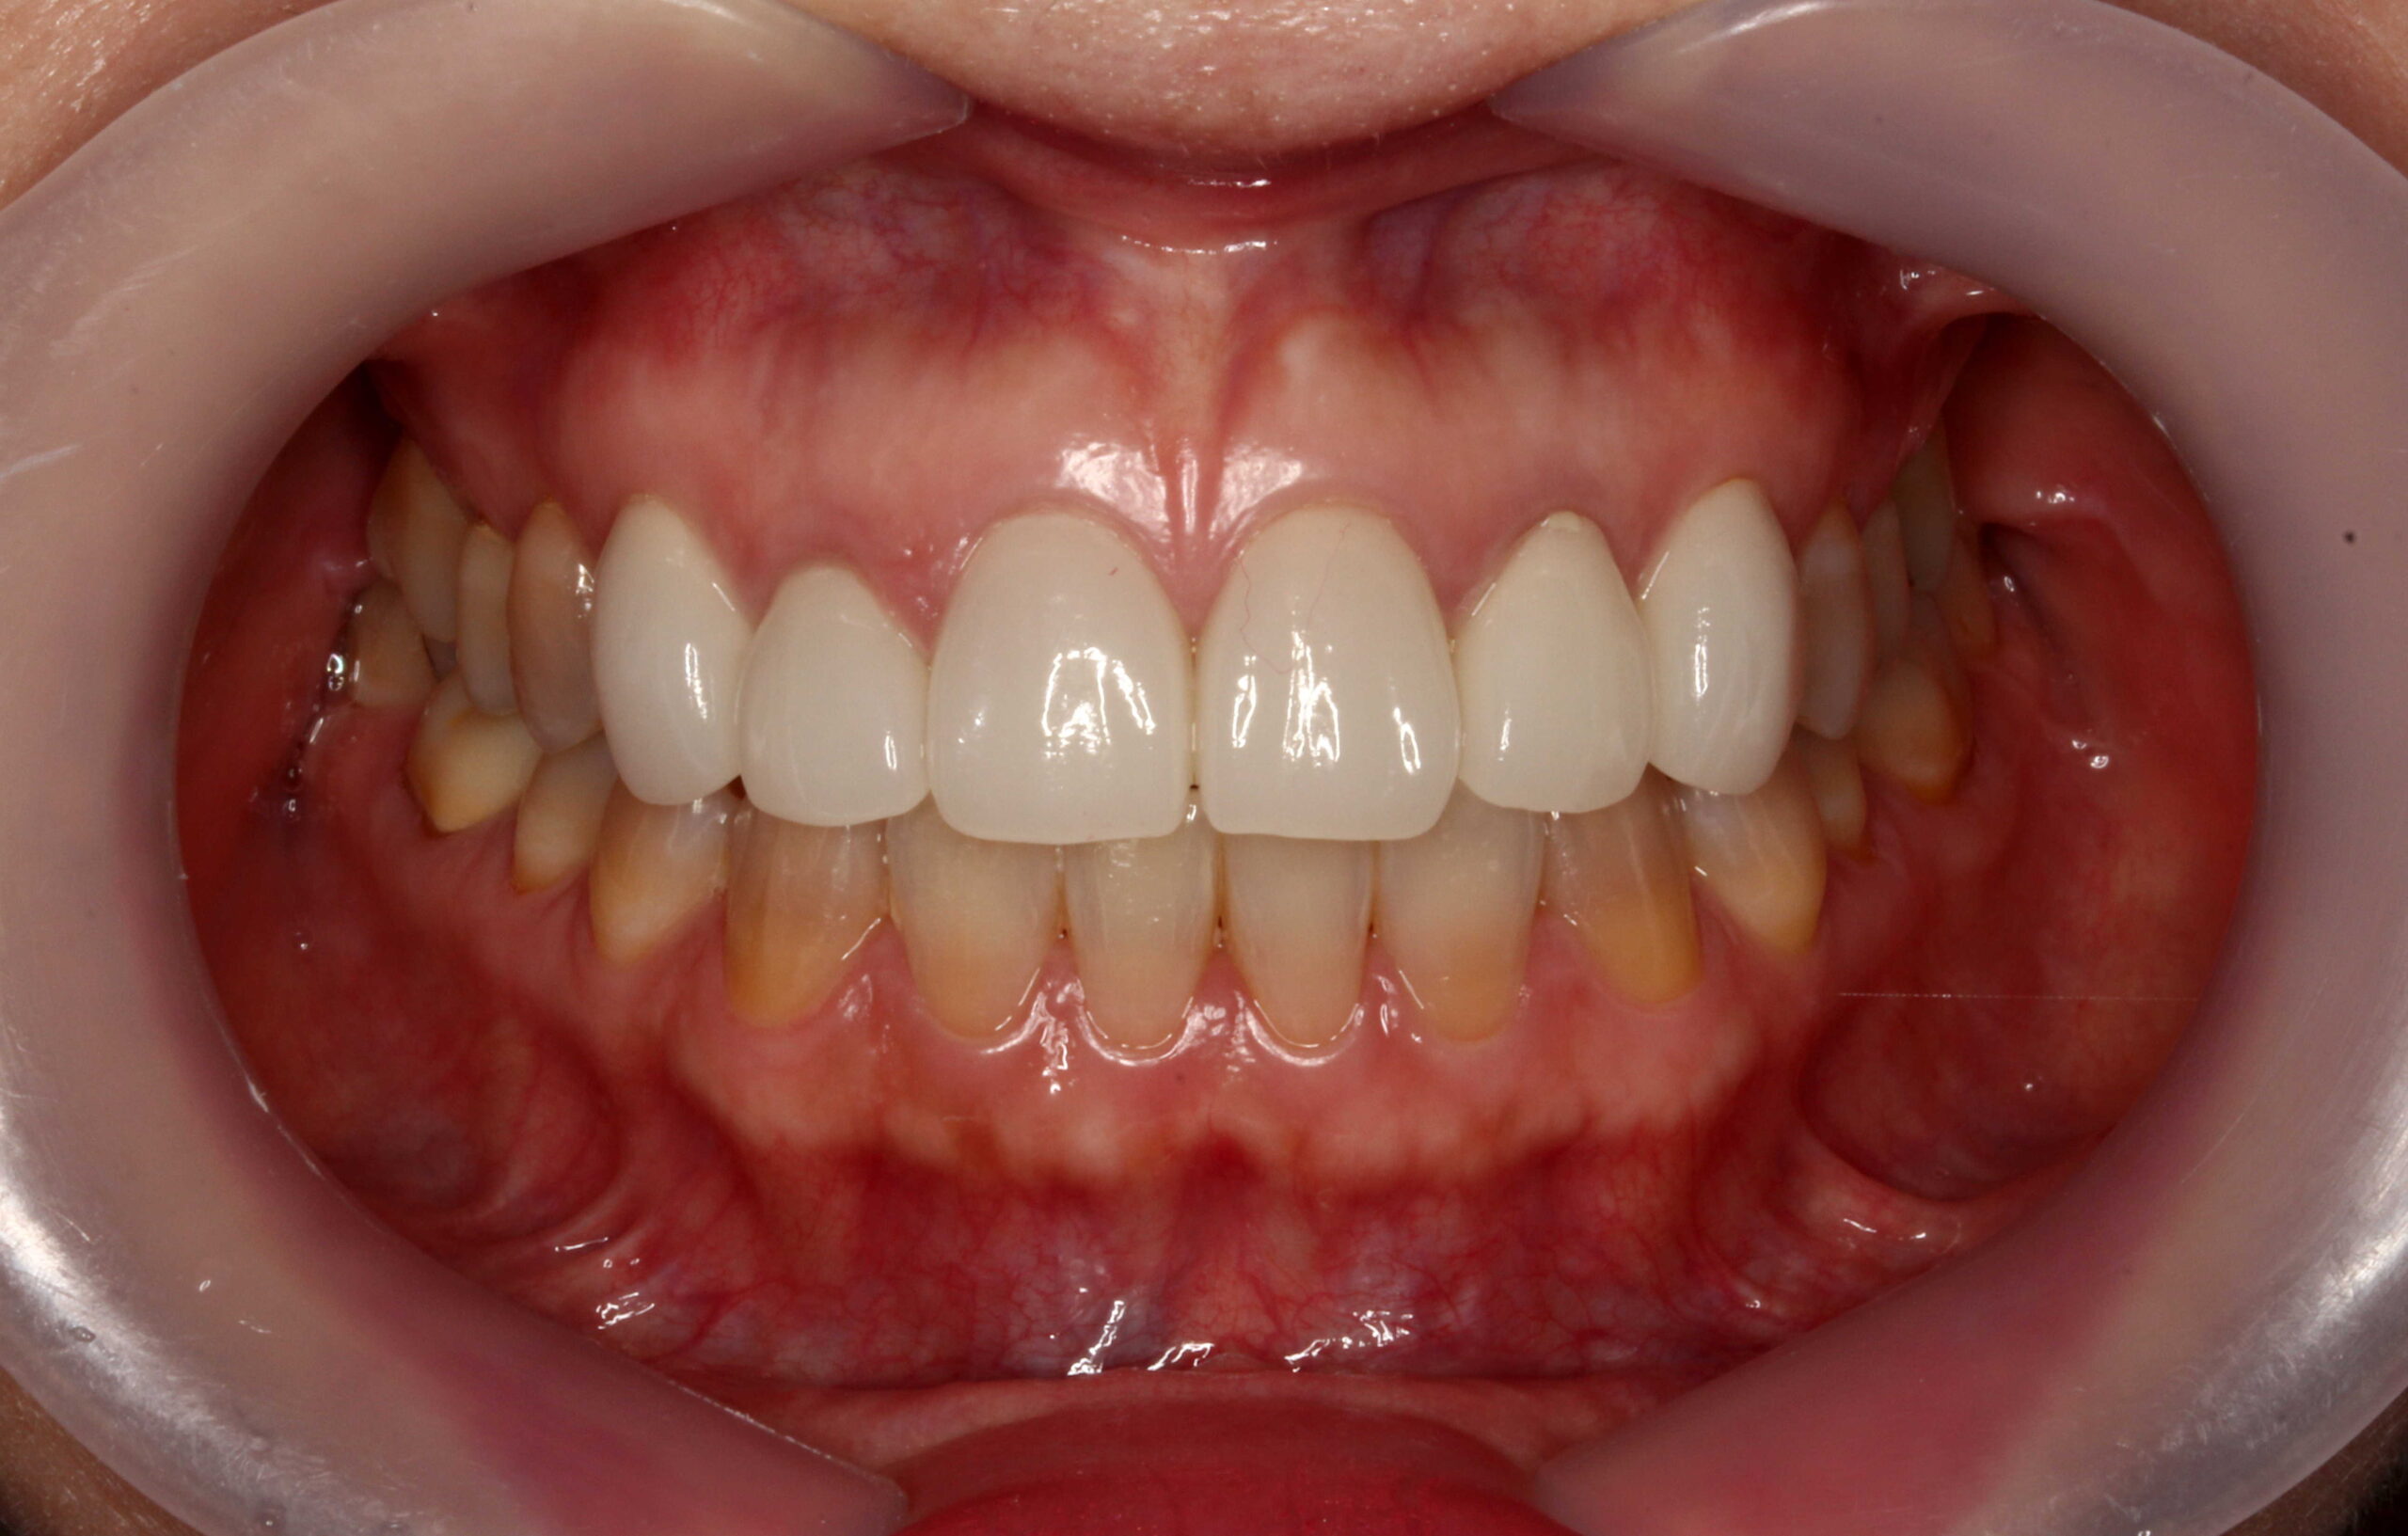

削らないラミネートベニアは、体に優しい健康的な審美歯科です。

丸の内 帝劇デンタルクリニック では、より低侵襲で体に優しい、健康を犠牲にしないような審美歯科治療が望ましいと考えています。

審美歯科の選択肢として、ホワイトニングやクリーニング、矯正治療や削らないラミネートベニア(NonPrepVeneer)などの「歯をできるだけ削らない方法」で「健康的な方法」を提案すべきと考えています。